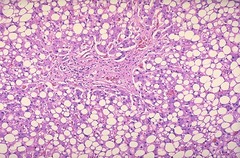

hepatic lipid accumulation

Front

organ? issue?

Back

-Hydropic degeneration of the liver -accentuated lobular pattern; pallor-light pink

Describe this liver